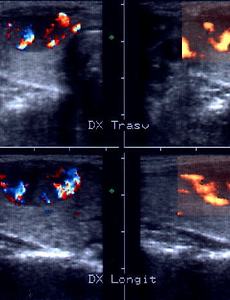

THYROID ADENOMA Woman, 32 y.o. Solitary nodule (mm 12x17x25) in the apex of the right lobe, hypoechoic, dishomogeneous owing to interior hyperechoid and hypoechoid areas; borders are regular. Colordoppler scan (left): rich internal vascularization, more evident in the powerdoppler scan (right) FNA: follicular neoplasm. Histological examination: microfollicular adenoma with trabecular aspects. Ultrasound tomogra.. 2009. 9. 21. 이전 1 다음